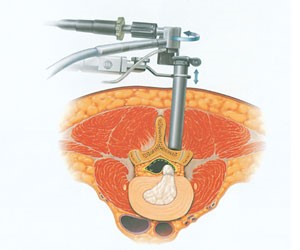

脊椎内視鏡手術

脊椎内視鏡手術とは、脊椎疾患に対して内視鏡を用いて、少ない侵襲で手術を行う方法です。

従来、骨や靭帯を切除して神経の圧迫を除去するために、内視鏡を用いることで必要最小限の切開で済むようになり、低侵襲の手術が可能になります。

術式

全身麻酔下で、小切開を行い、内視鏡を用いて手術を神経モニタリングをしながら、神経を圧迫している骨や靭帯の切除、ヘルニアの摘出を行います。